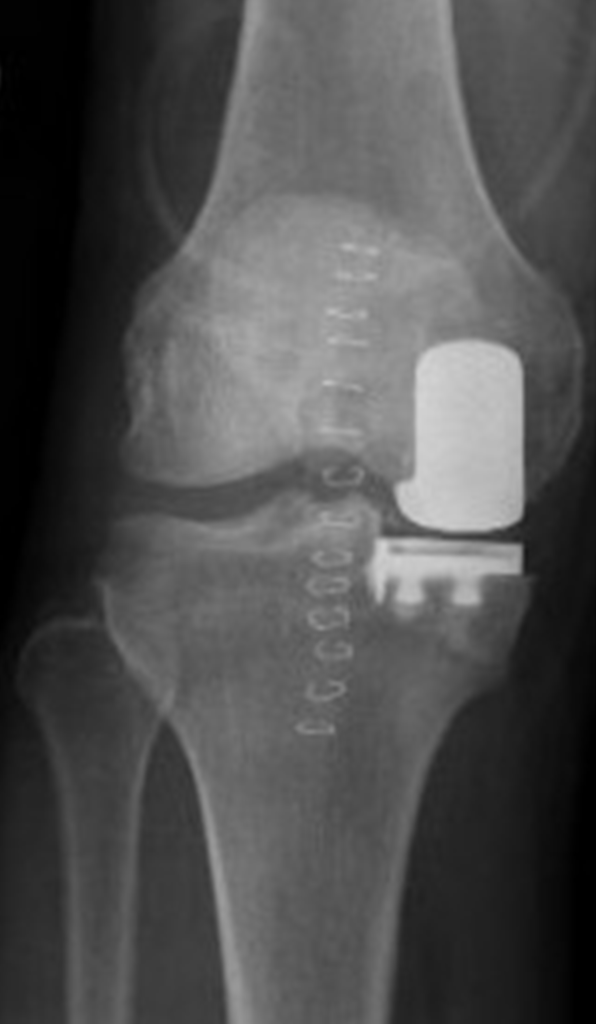

kneereplacementxray The Orthopedic & Sports Medicine Institute in Contour Knee Replacement He specializes in performing knee and shoulder reconstruction, ligament. Surgical reconstruction or replacement due to failure or complications of. Conformis designs and manufactures customized knee and hip replacements specifically for each individual patient to help surgeons deliver better outcomes. Find out what a knee replacement involves, when it might be recommended, and how it can help with knee pain and. Contour Knee Replacement.